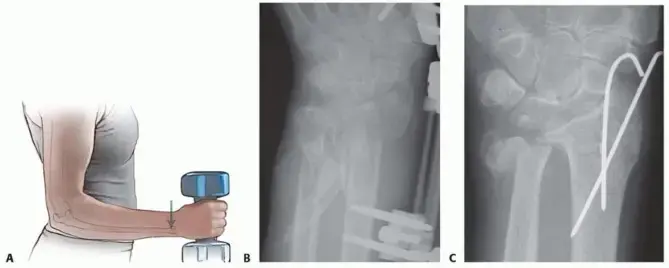

ما هي عملية الرد المفتوح والتثبيت الداخلي (ORIF)؟

هذه العملية هي المعيار الذهبي لعلاج الكسور المشردة وغير المستقرة.

1. الرد المفتوح (Open Reduction): يقوم الجراح بإجراء شق جراحي للوصول إلى العظام المكسورة. ثم يقوم بإعادة محاذاة أجزاء العظم المكسورة بدقة إلى وضعها التشريحي الطبيعي. هذا يضمن أن المفصل سيعمل بسلاسة بعد الالتئام.

2. التثبيت الداخلي (Internal Fixation): بمجرد إعادة العظام إلى مكانها، يقوم الجراح بتثبيتها باستخدام أدوات خاصة مثل:

• الصفائح والمسامير (Plates and Screws): غالبًا ما تُستخدم صفائح معدنية رفيعة مصنوعة من التيتانيوم أو الفولاذ المقاوم للصدأ، تُثبت على العظم بمسامير صغيرة. هذه الأدوات تعمل كـ "دعامات" داخلية تحافظ على استقرار العظم أثناء التئامه.

• الأسلاك أو الدبابيس (Wires or Pins): في بعض الحالات، خاصة لكسور الناتئ الإبري أو الكسور الصغيرة، يمكن استخدام أسلاك رفيعة لتثبيت الأجزاء المكسورة.